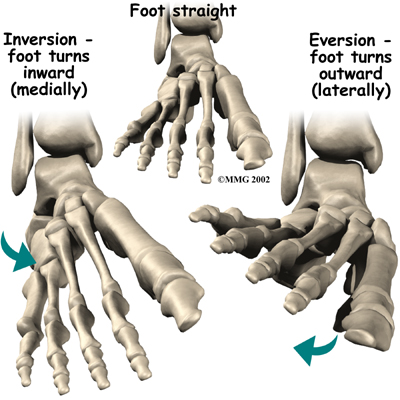

The lateral ligaments are by far the most commonly injured ligaments in a of the ankle. In an inversion injury the ankle tilts inward, meaning the bottom of the foot angles toward the other foot. This forces all the pressure of your body weight onto the outside edge of the ankle. As a result, the ligaments on the outside of the ankle are stretched and possibly torn.